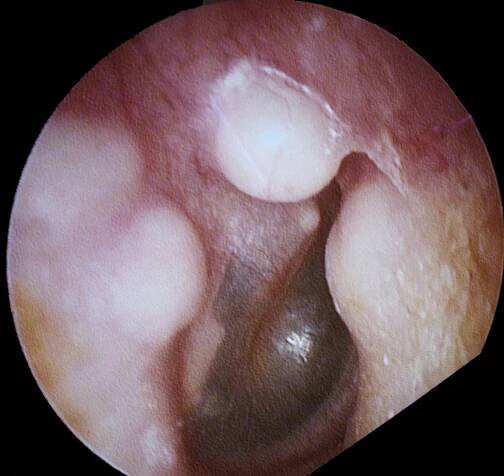

Tento obrázek ukazuje osteoidní osteom pozorovaný pod mikroskopem.